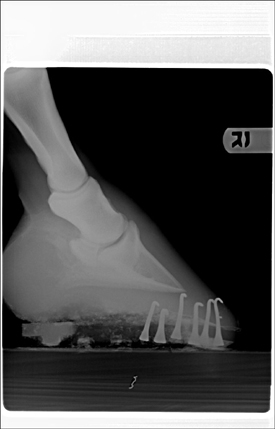

Posted on Wednesday, Mar 23, 2005 - 10:39 am: I'm having difficulty, but try this one. I could also email them to you, that way you'll get the full xray. Let me know if that's ok. |

Posted on Wednesday, Mar 23, 2005 - 10:41 am: Here's another one in case this works.

Posted on Friday, Mar 25, 2005 - 10:20 am: I can see he has remarkable calcification of the lateral cartilages (probably not significant) and the 10:41 image appears to have something going on around the coffin joint, but I cannot make out any detail.These images were originally 8 by 10 and for the detail we need, for the type judement you want, it is going to require a full size original on a screen, only then can I compare these lesions with those I have seen in the past. Let's try to get this on firmer ground. What lesions did your veterinarian diagnose from the above radiographs that made him make the above statement? DrO |

Posted on Tuesday, Mar 29, 2005 - 11:22 am: You appear to be making sense but I don't understand the vets thought about degenerative joint disease of the coffin bone bone healing: this is chronic arthritis. Are you sure you are on the same wavelength with your vet?Looking at your radiographs only raises more questions. Looking at rf2, which is an oblique of the foot, at first glance looks like changes consistant with coffin jt arthritis but...we have to remember that the lateral cartilages are ossified. For those follwing this discussion it is the 10:41 am radiograph above. I cannot be sure we are not seeing the overlying lateral cartilage, making it appear that the joint has developed remarkable osterphytes. In fact I find this a likely explanation but would require further radiography to prove or disprove. I don't see evidence of DJD of the coffin joint evident on the lateral (straight from the side) or ap (the one taken directly from in front of the foot) and the other obliques are too underexposed to read this aspect of the study. Though we do not see it in the other views, often the first place to see these changes are in the oblique shots. I recommend the vet take a series of obliques that slowly work around the foot to differentiate these 2 possiblilities. Yes you can palpate the side bone. Look on the ap radiograph and it will show you exactly where to feel them. DrO |

Posted on Thursday, Apr 7, 2005 - 10:02 am: Assuming we are talking about the same thing, I disagree with your veterinarian. If you look closely at the side bone in the first (lateral) radiograph there is a little notch at the top. In the second (oblique) shot the area that looks like severe DJD changes of the coffin joint also has a notch at the top: they look like the same notch to me.I don't think the relationship of the coffin bone to most of the sole is bad, but agree with the farrier, the toe needed chopping off in front. Just off the front, I would not thinning the sole uner at the toe. DrO |

Posted on Friday, Apr 8, 2005 - 9:41 am: No not a bone spur, in one of the obliques what looked like severe osteoarthritis of the coffin joint appears in these later images to be artifactual, and instead the superimposed calcified cartilages. Given that I am loking at images in a low resolution environment, I don't see evidence of coffin joint arthritis.DrO |